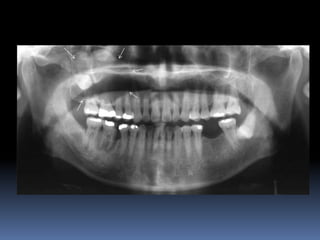

Dental Panoramic Tomography

(Panoramic Radiography,

Orthopantomography And Rotational

Radiography)

In panoramic tomography, the section or focal

plane is designed to be approximately

horseshoe shaped; corresponding to the

shape of the dental arches.

 Produces a single tomographic image of facial

structures including both maxillary and

mandibular arches and their supporting

structures.

 The radiation dose is relatively low; the dose is

equivalent to about three to four perapical

radiographs.

 However, there is distortion and magnification of

the final image.

 Image quality is inferior to that of intraoral